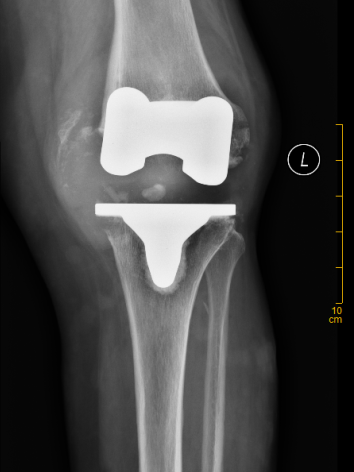

经详细查体,发现陈女士左膝关节肿胀明显、内翻畸形,关节脱位,无法行走,X线片显示,假体松动,内侧股骨髁、内侧胫骨平台部分骨溶解,左下肢内翻畸形,确诊为“左侧人工膝关节置换术后假体松动”并收住晋江市医院骨科。

▲ X线提示:假体松动,内侧股骨髁、

内侧胫骨平台部分骨溶解,左下肢内翻畸形